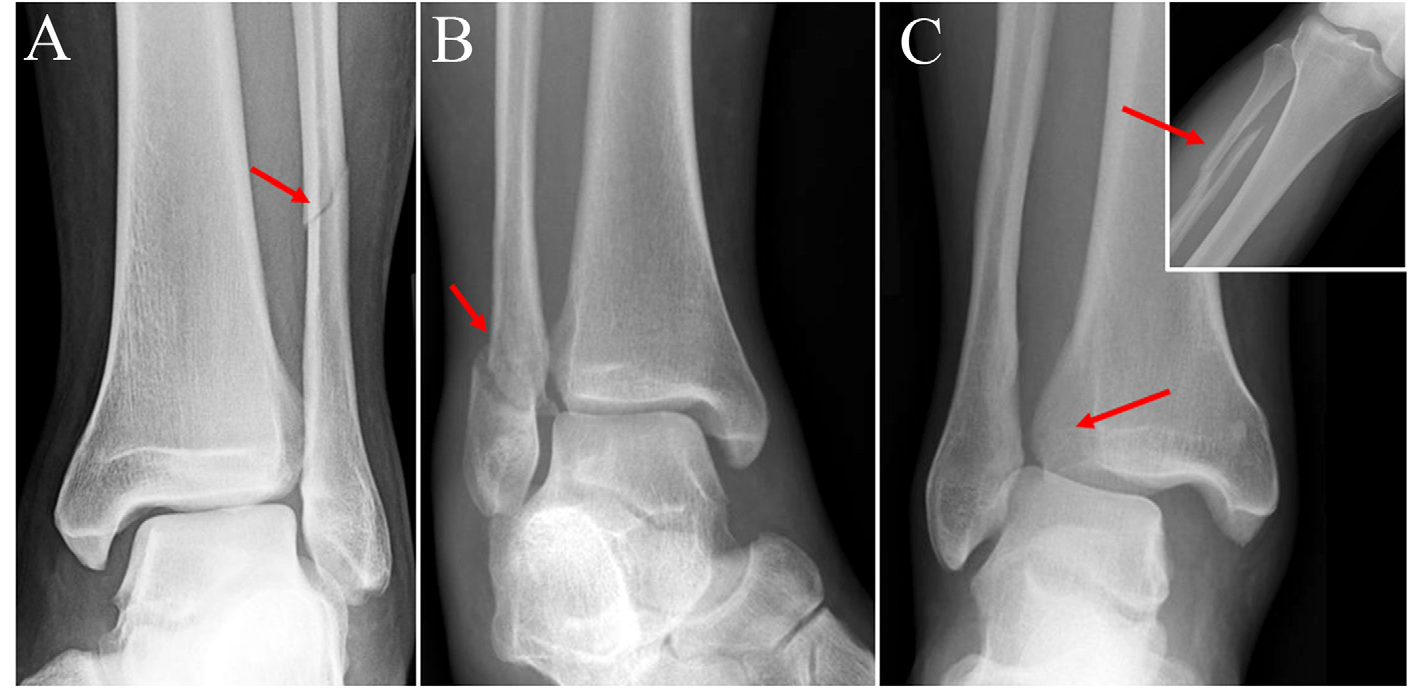

- Radiografias (Raios-X): As radiografias iniciais podem mostrar um alargamento do espaço entre a tíbia e a fíbula (diástase) ou fraturas associadas. No entanto, muitas vezes, em repouso, as radiografias podem parecer normais, mesmo com uma lesão significativa.

A lesão da Sindesmose só ocorre associada a fraturas?

Não! Embora a lesão da sindesmose seja frequentemente associada a fraturas do tornozelo (como as fraturas de Maisonneuve ou certas fraturas de Weber B e C), ela pode ocorrer de forma isolada.

- Lesão Associada a Fraturas: Nesses casos, a força que causa a fratura do tornozelo também afeta os ligamentos da sindesmose, resultando em uma lesão combinada que exige atenção redobrada no tratamento.

- Lesão Isolada: Uma lesão isolada da sindesmose ocorre sem que haja nenhuma fratura óssea aparente no tornozelo. Essas lesões são muitas vezes as mais desafiadoras de diagnosticar, pois podem ser confundidas com uma entorse de tornozelo comum. Por essa razão, a importância da tomografia com carga simulada é ainda maior nesses casos, pois ela pode revelar a instabilidade que não é vista em exames convencionais.

É vital que o médico ortopedista saiba diferenciar esses tipos de lesão, pois o tratamento e o prognóstico podem variar significativamente. A falha em diagnosticar uma lesão isolada da sindesmose pode levar à instabilidade crônica do tornozelo, dor persistente e artrose precoce.